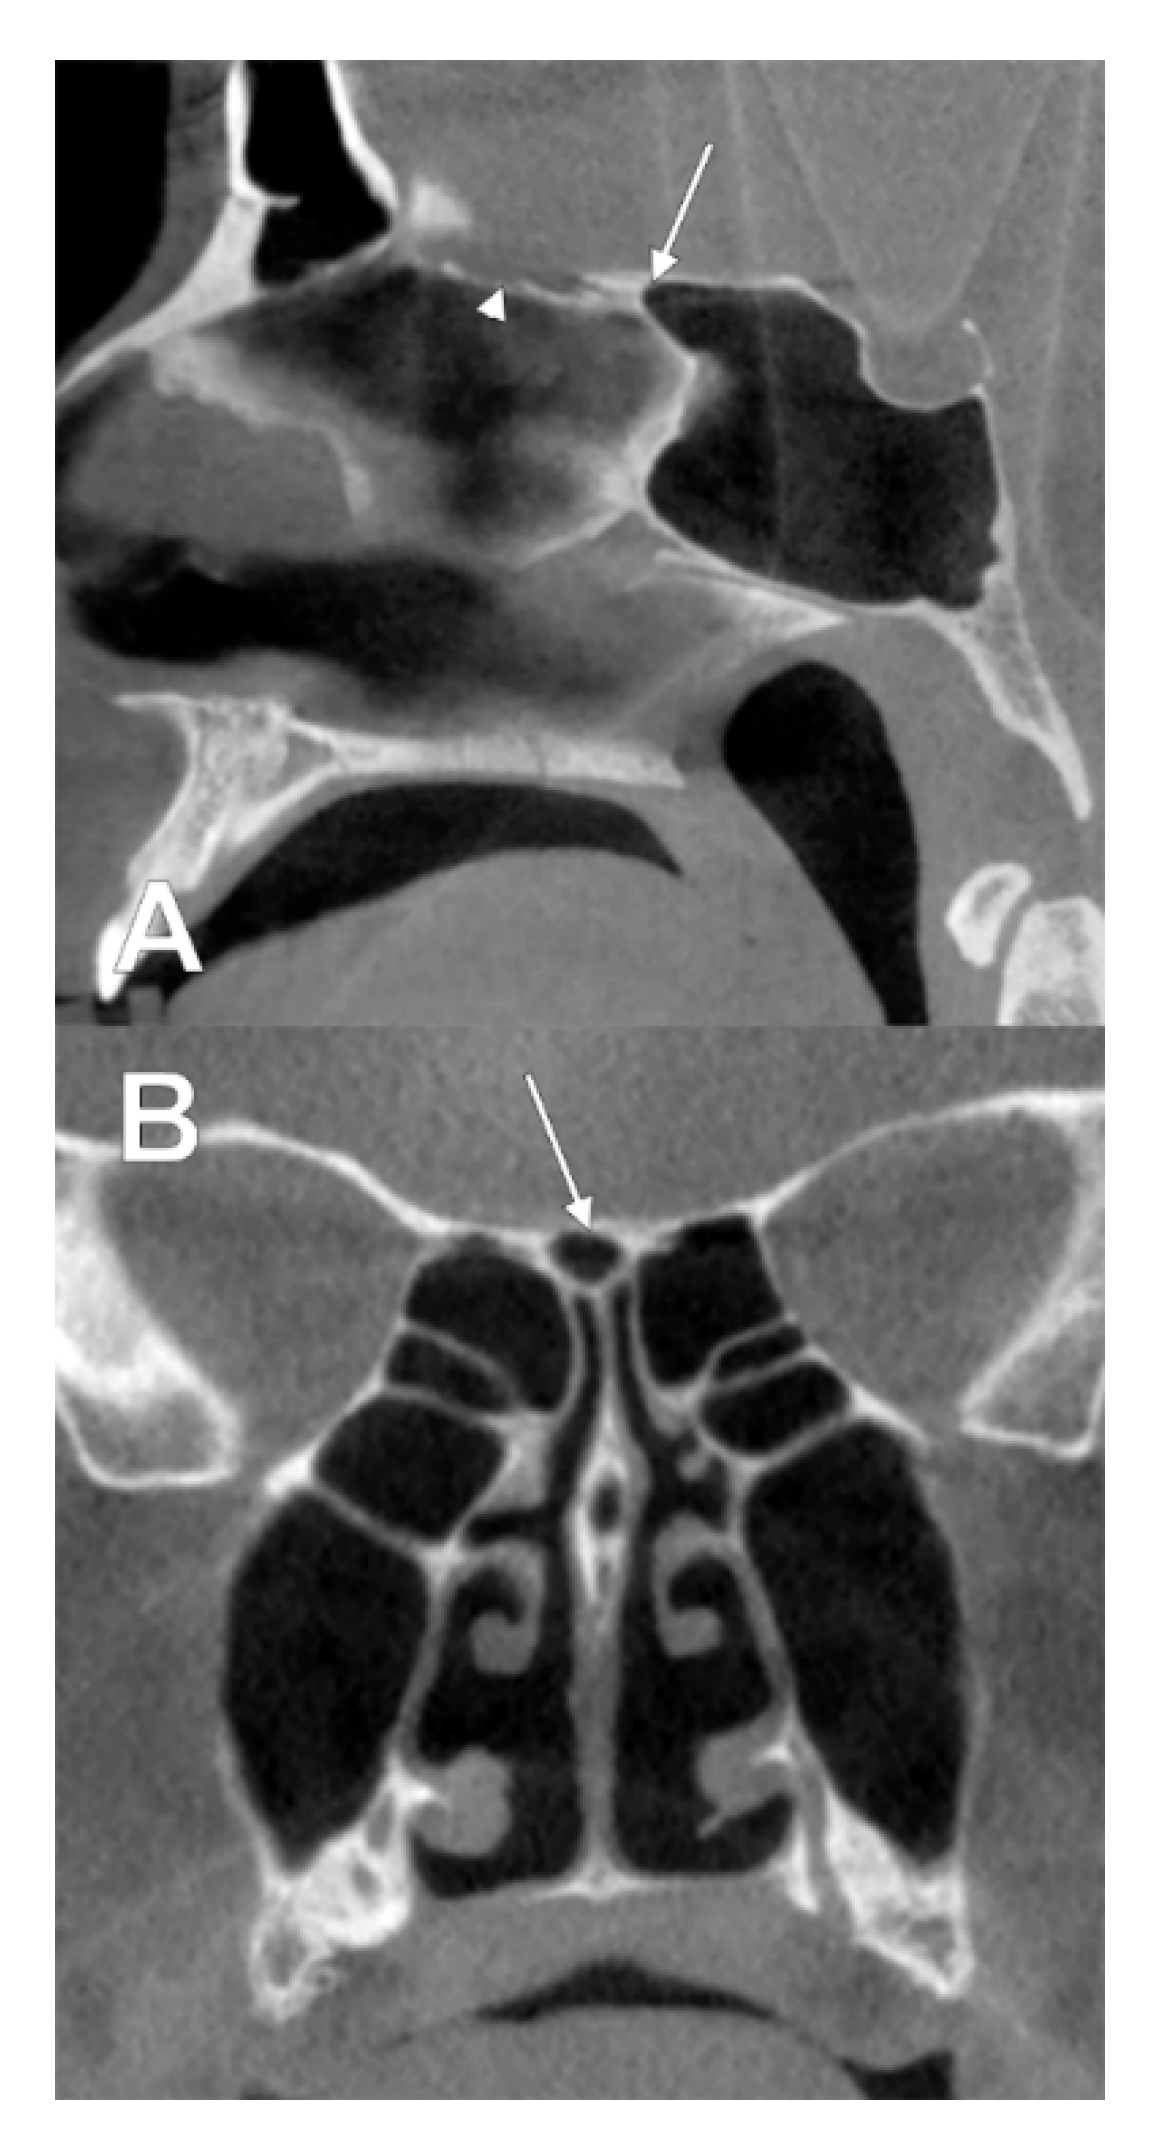

3.3. Sphenoethmoidal (Onodi Cell) Origin of Nasal Roof Pneumatizations

4. Discussion

4.1. Gore’s Supraseptal Air Cell